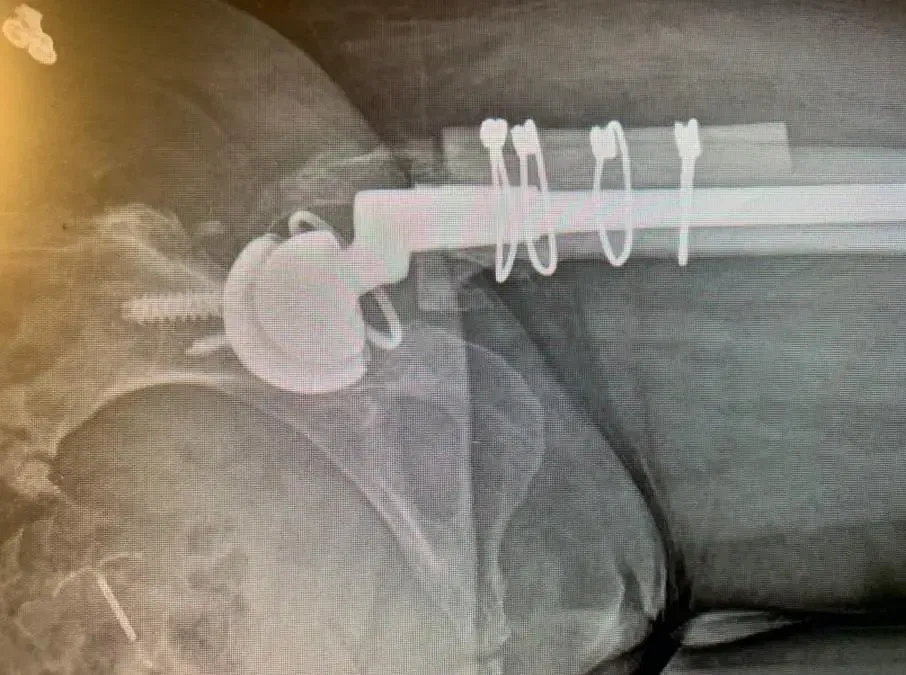

El paciente es un varón de 55 años que acudió a nosotros quejándose de luxación recurrente de prótesis de cadera derecha. El paciente declaró que esto había estado ocurriendo desde que tuvo una artroplastia total de cadera derecha (THA) hace unos años realizada en una...